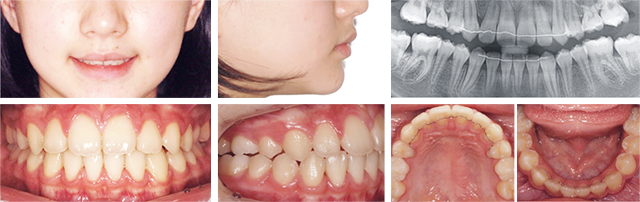

덧니가 보기 좋지 않고 앞니끼리 물린다는 주소로 내원한 청소년. 진단 결과 위턱에 비해 아래턱의 성장 량이 더 나타나는 골격성 3급 부정교합이 확인되었고 성장 완료 후 악교정 수술을 고려할 수 있으나 사춘기 여학생임을 감안하여 이를 가지런히 하고 교합 관계를 개선시킨 후 주기적으로 관찰하는 계획을 세워 진행하였습니다.

좁아져 있는 악궁을 확장시켜 치아를 배열할 공간을 확보하고, 전방 위치된 아래턱으로 인해 어긋나 있는 교합 관계를 개선하기 위해 특수한 형태의 와이어(MEAW-Multiloop Edgewise Arch Wire)를 이용하여 치료하였습니다.